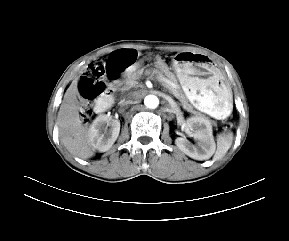

标题: CT19533:病变来源于哪?

患者,男,发现上腹部包块两月余。

病变位于肝胃间隙,实际就是位于小网膜囊(左肝下后间隙),呈轻度不均匀性强化,腹腔内及腹膜后见多发肿大淋巴结。所以我考虑肝胃间隙恶性胃肠间质瘤并淋巴结转移。

病灶强化不显著,灶周及腹膜后见多量淋巴结肿大,考虑淋巴瘤可能,其次考虑间质瘤

肝胃韧带内及腹膜后可见多发增大的淋巴结影,首先考虑转移.